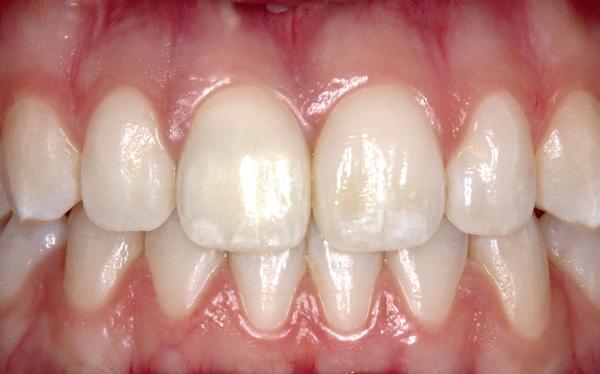

Een patiënt die conventioneel tandheelkundig vrijwel volledig is uitbehandeld, stelt de behandelaar voor complexe keuzes. In dit artikel wordt aan de hand van een uitgebreide casus beschreven hoe diagnostiek, prognosebepaling en interdisciplinair overleg leiden tot een voorspelbaar implantologisch behandeltraject. De casus illustreert hoe een ogenschijnlijk onsamenhangende restauratieve voorgeschiedenis kan uitmonden in een doordacht en succesvol full-arch implantaatgedragen rehabilitatieplan.

In de prothetische fase (zie foto’s) is in de bovenkaak gebruikgemaakt van verschroefde zirconia bruggen, die enkel buccaal zijn opgebakken. Deze bruggen zijn verlijmd op individuele, geanguleerde titanium abutments. In de onderkaak is een verschroefde kunststofbrug op een titaniumbasis (wrap-around) gemaakt. Voor deze combinatie is gekozen vanwege een minder hinderlijk tikkend geluid bij functie en kleinere kans op breuk van de keramiek. Een nadeel is verhoogde slijtage van de kunststof elementen, maar deze zijn in de jaren later eenvoudig te vervangen op de bestaande brug. Ondanks alle digitale mogelijkheden is de afdruk en registratiefase analoog uitgevoerd, omdat in ervaring van de behandelaren dit bij deze totale rehabilitaties op implantaten nog altijd de grootste precisie oplevert. Er is afgedrukt met impregum in individuele lepels en de pasvorm is gecontroleerd met rigide duralay bars. De relatie wordt vastgelegd zoals bij een volledige prothese met waswallen en pijlpuntregistratie. De opstelling in was wordt gepast en laatste correcties worden gemaakt in samenspraak met de patiënt, de restauratieve tandarts en de tandtechnicus. Na het vastzetten van de suprastructuren worden de schroefgaten afgesloten met composiet.